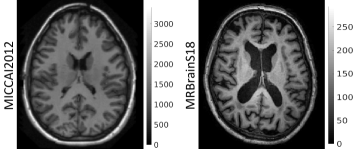

Figure 1: T1-weighted MR images from two different, publicly available, datasets: MICCAI2012 and MRBrainS18 (on which we evaluate our method). It is evident that learning from one of these populations, and subsequently testing on the other is very challenging. The intensities are different by an order of magnitude, the bias is stronger in the MRBrainS18 subject. Additionally, age related change and pathology can be clearly seen, such as differences in ventricle size and white matter hyper-intensities, which further complicates the learning problem.

Challenges on medical image segmentation can be seen as lab experiments and – as with new medical therapies – there is a large gap to get from bench to bedside. CNNs excel in this context, factorising the commonalities in an image population of training data, which generalise to new data from the same population. They can struggle, however, when faced with new data that contain unseen features [10], e.g., a different contrast (Fig. 1). This scenario usually requires the model being trained anew, on that unseen image contrast. In fact, even without considering inter-individual variability (age, brain shape, pathology, etc), a CNN-based segmentation software has yet to be presented that is agnostic to the great variability in MR data [11]. Lack of such software is largely due to the limited amount of labelled data available in medical imaging, which is a clear obstacle to their generalisability. Some methods have been developed to address this problem, e.g., intensity normalisation [12], transfer learning [13] and batch normalisation [14]. Still, none of these methods are yet general enough to solve the task of segmenting across scanners and protocols. Recently, approaches based on realistic data augmentation have shown promising results [15, 16].

Within each dataset, all subjects were scanned on the same scanner and with the same sequences, whilst between datasets, the scanners and sequences differ (Fig. 1). Both datasets have multiple labelled brain structures, such as cortical GM, cerebellum, ventricles, etc. We combined these so as to obtain the same three labels for each subject: GM, WM and OTHER (1GMWM1GMWM1-\text{GM}-\text{WM}). These labels were used as targets when training our model.